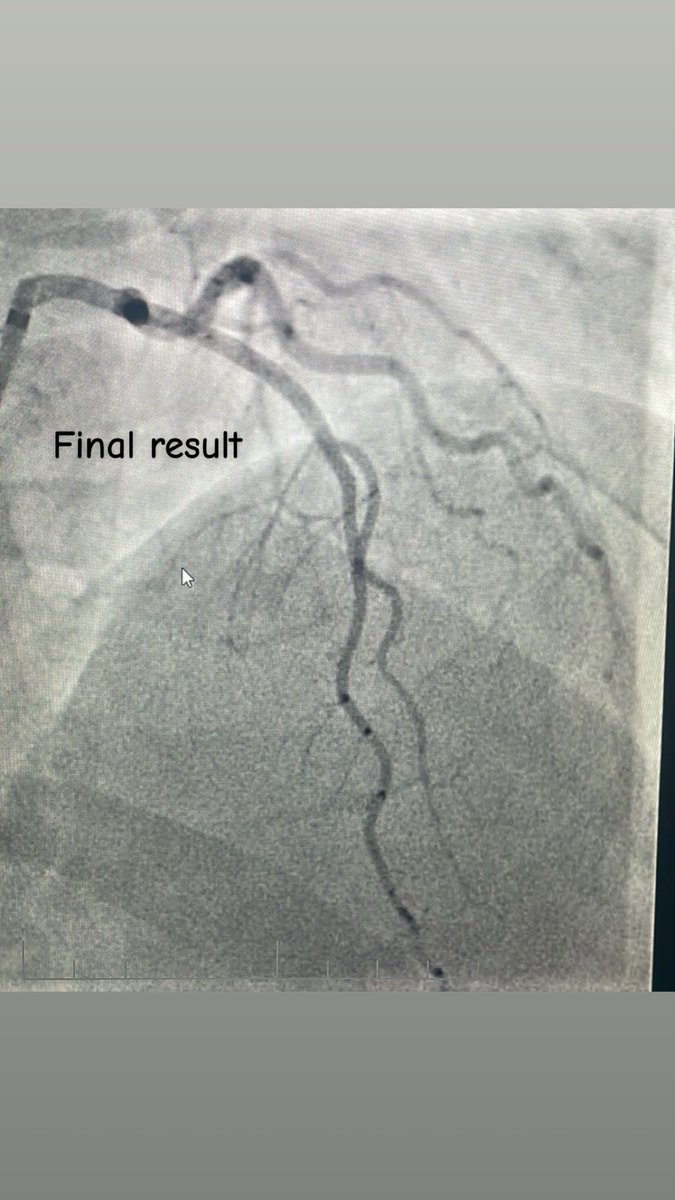

CTO LAD 🔹Dual injection 🔹RCA with wire protection 🔹LAD with microcatheter 🔹Trapping technique to secure the wire 🛑 Always secure the donor first 📍 Microcatheter = Stability + Roadmap ⚠️ Don’t rush the setup, good prep = smoother case 😁 Happier than the patient. #CTO…